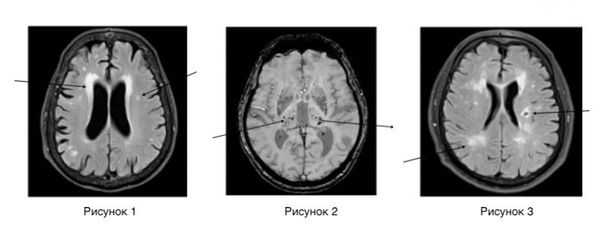

(а) МРТ, FLAIR, аксиальный срез: у мужчины 35 лет с «нейро-Бехчетом» определяется повышение сигнала от левых вентральных отделов среднего мозга с умеренным увеличением их размеров, а также отдельные очаги в правых его отделах. Это хроническое рецидивирующее идиопатическое полисистем-ное сосудисто-воспалительное заболевание также характеризуется развитием орогенитальных изъязвлений.

(б) МРТ, постконтрастное Т1-ВИ, аксиальный срез: у этого же пациента определяется контрастное усиление крупного участка повреждения среднего мозга. Визуализационная картина сходна с таковой при новообразовании, васкулите и демиелинизирующем заболевании.

(а) МРТ этого же пациента, выполненная через два года, FLAIR, аксиальный срез: разрешение изменений в области левых отделов среднего мозга, а также появление крупного очага в правых его отделах с распространением на соответствующую ножку мозга. Рецидивирующеремиттирующее течение типично для данного заболевания.

(б) МРТ, FLAIR, аксиальный срез: у молодого мужчины, страдающего изъявлениями слизистой полости рта, с болезнью Бехчета определяется повышение сигнала от вещества моста в сочетании с умеренным увеличением его размеров. Другие очаги поражения были выявлены в среднем мозге и базальных ганглиях. Для этого заболевания поражение таламуса и белого вещества больших полушарий менее характерно.

Нейровизуализационные методы: КТ, МРТ головного мозга, МР-ангиография (артерии и вены головного мозга ), при необходимости рентгеноконтрастная церебральная ангиография. Нейровизуализация позволяет исключить другие заболевания (опухоль, гидроцефалию) и подтвердить сосудистый характер нарушений. Предпочтительнее МРТ головного мозга, на которой выявляются характерные для хронической ишемии мозга изменения:

- лейкоареоз — изменение белого вещества вокруг желудочков головного мозга (на рисунке 1, белое свечение вокруг желудочков);

- лекоэнцефалопатия — поражение белого вещества головного мозга (на рисунке 1 и 3, светлые участки в подкорковом веществе);

- малые инфаркты, ишемические инсульты (рисунок 3);

- множественные микрокровоизлияния (рисунок 2 — темные участки);